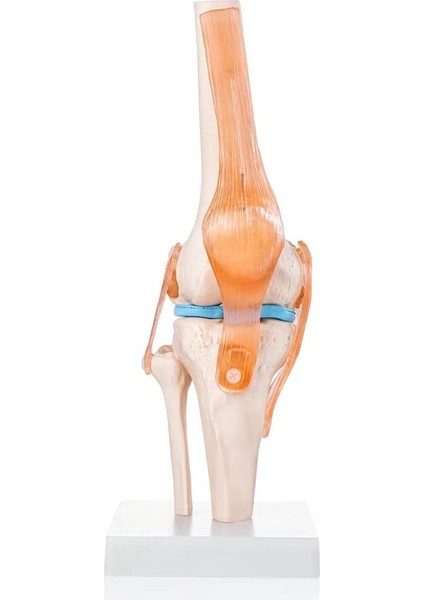

Egeanatomi Maketleri Diz Eklemi Modeli - Diz Eklemi Maketi

- Gerçek boydaki diz eklem modeli, fleksiyonu, ekstansiyonu ve iç-dış rotasyonu gösterir.

- Esnek ve yapay ligamentler içerir.

- Standı üzerinde durmaktadır.

- PVC malzemeden imal edilmiştir.

- Ölçüleri: 12x12x33 cm